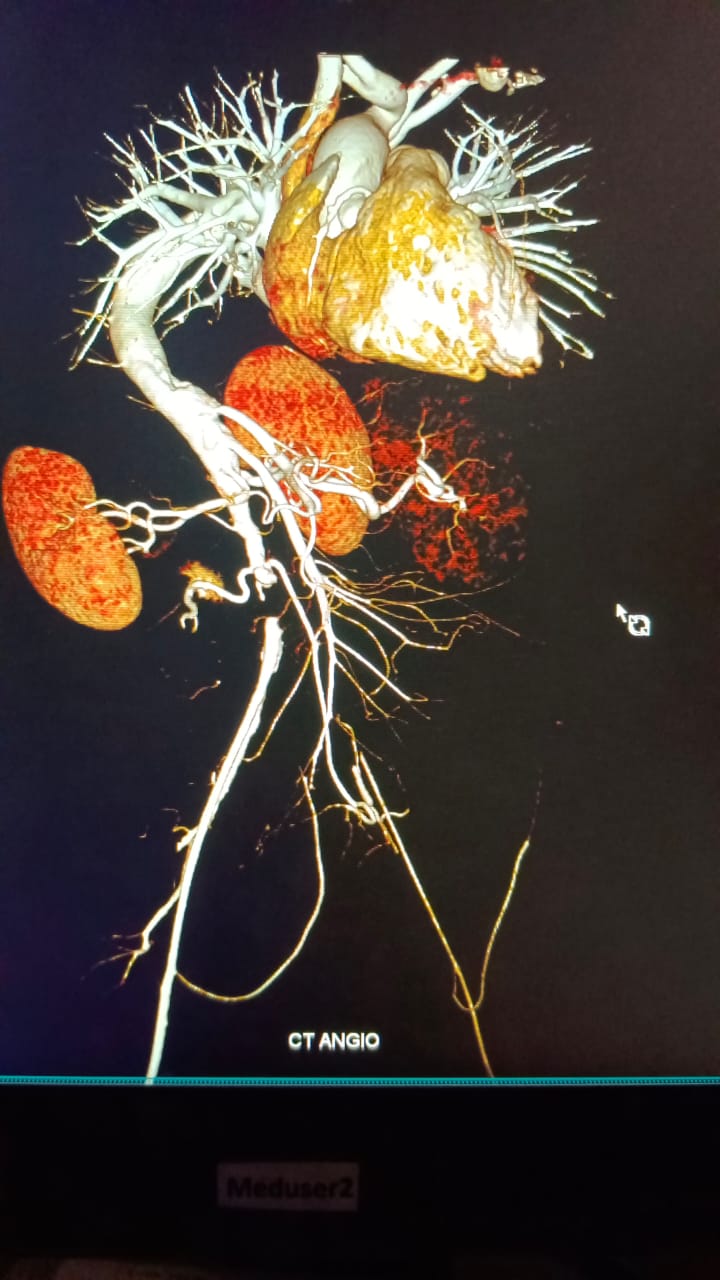

Access was right radial. It was difficult to cannulate the coronaries due to extreme kyphoscoliosis and dextroposition of the heart. Right femoral access was taken. As the teflon wire was not able to cross beyond the bifurcation of the aorta, we took a check angiogram which showed infrarenal abdominal aortic occlusion. Left main was normal. LAD mid segment was totally occluded. LCX-mild proximal disease. Proximal to mid RCA-70-80% stenosis.